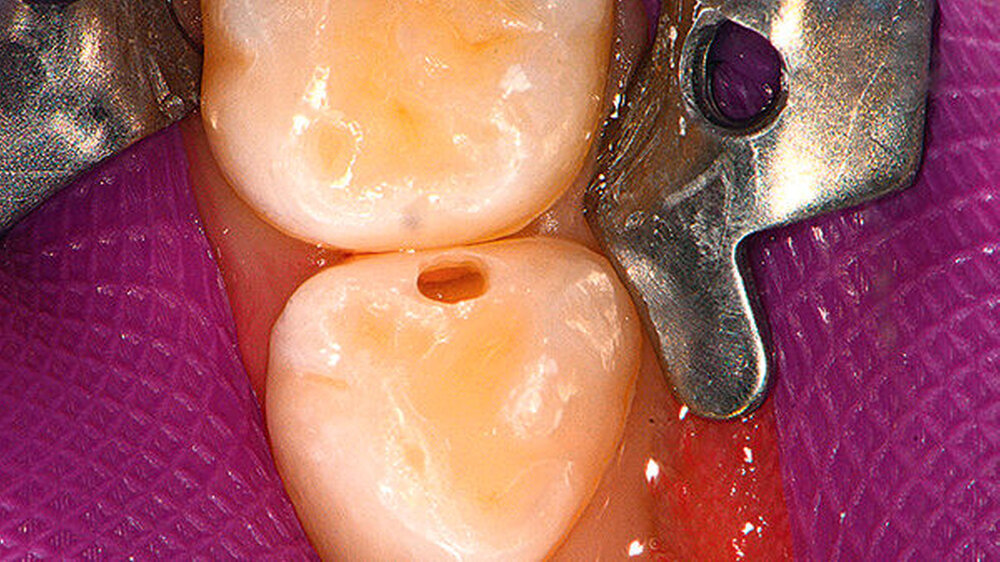

Leserbrief zum Beitrag: „Approximalkaries im Milchgebiss: Die versteckte Läsion“, zm 7/2017, S. 44–46.

Schön, dass Sie mit Frau Thumeyer auch einen kompetenten Interviewpartner aus der niedergelassenen Kinderzahnheilkundezunft gewinnen konnten. Ihr ist beizupflichten, dass ein Drittel aller Kinder eine Kontaktpunktkaries entwickelt, was aber leider im Gegensatz zu den Aussagen der DMS V-Studie steht, die medien- und politikwirksam von dem Erreichen von nahezu kariesfreien Milchzahngebissen träumt.